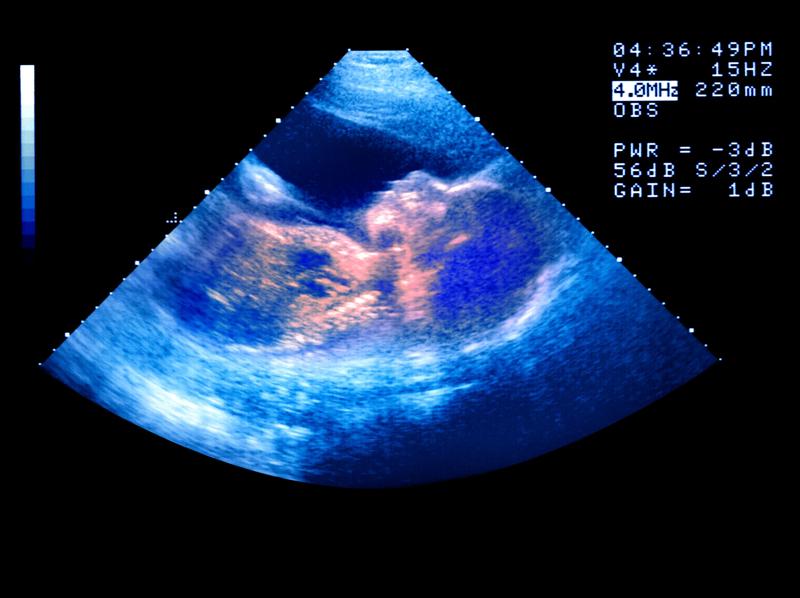

Babies may ‘catch’ yawns from their mother in the womb, new study finds

Researchers found that fetuses were more likely to yawn when their mother did, suggesting humans may experience yawn contagion throughout their life